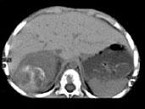

男孩,5岁。消瘦、贫血、纳差和腹部包块3个月余, CT如图所示,下列说法正确的是

A、右侧腹腔内可见一巨大软组织肿块影,其边界欠清楚

B、肿块密度不均匀,可见片状的较高密度,考虑为出血,也可见点状的钙化影

C、该病灶来源于肝脏,考虑为肝母细胞瘤

D、该病灶来源于右肾上腺,考虑为神经母细胞瘤

E、该病灶来源于右肾,考虑为肾胚胎瘤